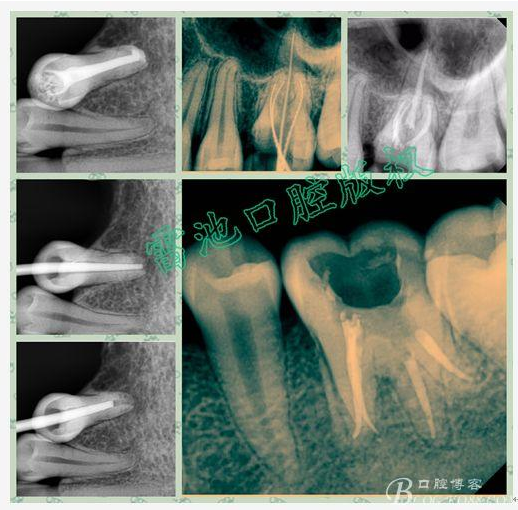

E 、X線影像學的檢查研判能力: 這點不需要強調太多,對于普通的非CBCT的二維影像對醫(yī)生讀片能力有一定的要求,有個逐步提高的過程,非一蹴而就,需要學會把二維的X線影像與三維的解剖結構進行良好的對應結合,對于某些鈣化的髓室底,應通過想象把根管口的分布、根管的走向以及各種變化通過想象投射到對應的髓室底上;

1、查閱各種文獻,MB2的發(fā)生率在52-96%之間,治療時遺漏是上頜磨牙根管治療失敗的主因,2、一般位于MB1根管口與腭根管口方向的0.5-5mm范圍內,而大多數都位于MB舌側的1-3mm處,其中2mm以內占85.7%,3、MB1-P根管口連線與MB1-MB2根管口的連線夾角大部分(74.3%)在30度以內;4、MB2的尋找大部分需要去除相應部位的牙本質;5、當找到的MB根管口呈“長線型”且有深色凹線向舌側,或者找到的MB根管口明顯偏頰多提示有MB2的可能;6、DOM(牙科手術顯微鏡)的使用有助于找尋MB2;

備注:為了更好的講解《根管治療的那些事兒(下)》(包括根管清理預備,沖洗,封藥,充填等問題),結合我這基層小診所的設備,我個人歸納總結一下除了以上某些小材料與設備,一般還需要準備如下設備與材料,相信會對大家提高自己的根管治療水平和效率有所幫助:

1、根管測量儀與電活力測定設備應該也是必備的:

診所測量儀應該多備點不同廠家的,一個可以作為備用機,另外在某些時候根測長度不穩(wěn)定時可以對照測定!